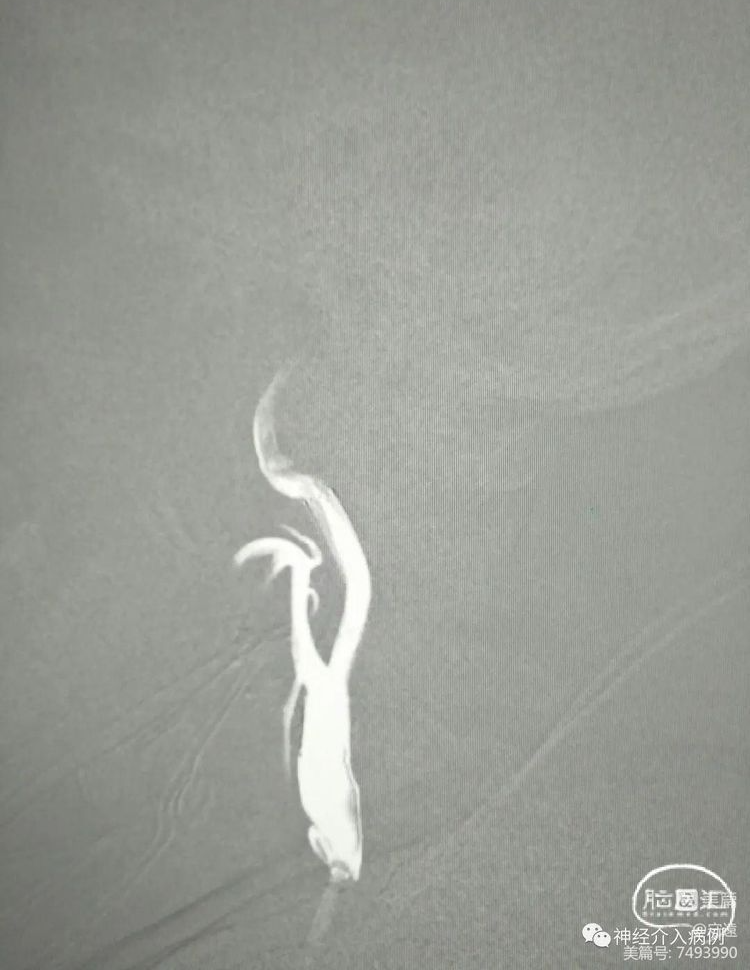

左侧颈内动脉起始部狭窄,血管走形迂曲。

术中保护伞下,(4×30mm)球囊预扩张,扩张时球囊充压8大气压,从心率75次迅速下降至45次,立即推注阿托品1mg,心率逐渐提升至65次分。

预扩张后置入锥形自膨式支架(8×30mm)。

术后血压降低为85/50mmHg。给予小剂量多巴胺3~5ug/Kg分,血压维持在120/60mmHg。